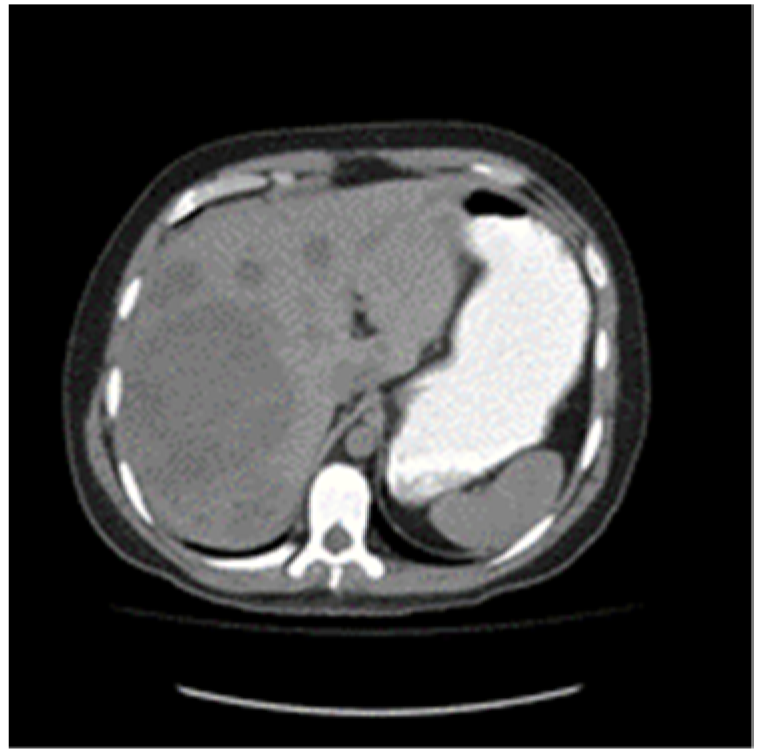

A 30-year-old patient awaiting a living-related donor renal transplant for chronic renal failure (creatinine 571 umol/L) related to reflux nephropathy presented to the local emergency room with right upper quadrant pain. Laboratory investigations revealed elevated liver function tests with hepatomegaly on abdominal ultrasound and multiple hepatic masses suspicious for metastasis. Subsequent computed tomography of the chest, abdomen, and pelvis confirmed multifocal hepatic lesions (Figure 1), periportal lymph nodes, a 4-mm nonspecific left lower lobe lung lesion, sclerotic lesions of the ribs, and a large mass in the left scrotum consistent with a testicular cancer (Figure 2). Bone scan also demonstrated sclerotic lesions in the seventh thoracic vertebrae, sternum, and the left iliac bone. Physical exam confirmed a large right testicular mass. His alpha fetal protein (AFP) was 62,777 umol/L (normal < 10), Beta-human chorionic gonadotropin (B-HCG) was 32 IU/L (normal < 1), and the lactic acid dehydrogenase (LDH) was 367 U/L (normal < 192).

Figure 1. Baseline unenhanced CT scan showing multiple liver metastases.